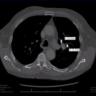

Lung - Cancer